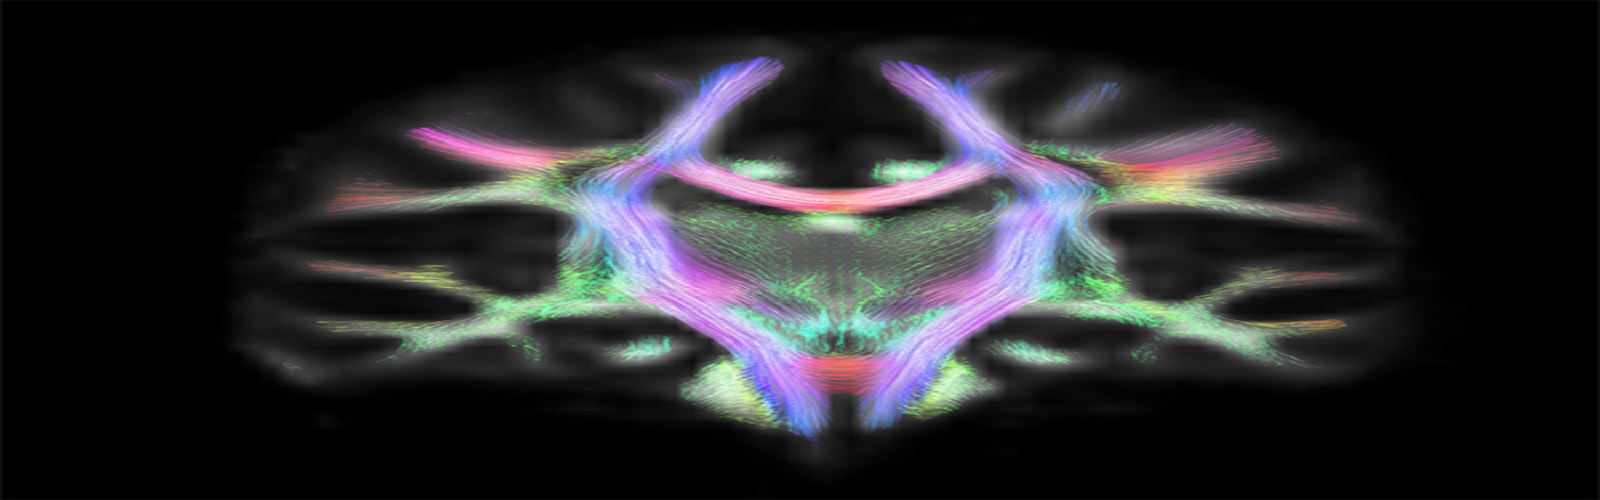

1. Tripathi, A., Jose Guerrero Gonzalez, Traci Snedden, Alison Brooks, Peter Ferrazzano, Christian Franck, Rika Carlsen, 2022. Effect of Individual Anatomical Differences in Brain Deformation From Head Accelerations: A Computational Study. International Mechanical Engineering Congress and Exposition, ASME, Columbus, Ohio, USA.

1. Tripathi, A., Jose Guerrero Gonzalez, Traci Snedden, Alison Brooks, Peter Ferrazzano, Christian Franck, Rika Carlsen, 2022. Effect of Individual Anatomical Differences in Brain Deformation From Head Accelerations: A Computational Study. PANTHER Meeting. University of Wisconsin Madison, Madison, Wisconsin, USA.